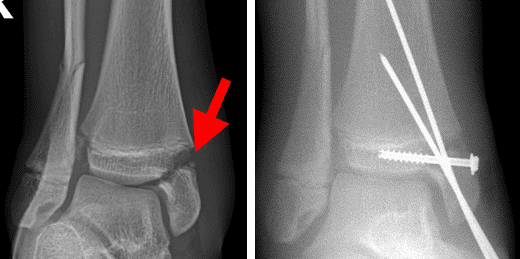

Tillaux fracture

In this Tillaux fracture, the blue arrow shows a widening of the growth plate, and the red arrow shows the fracture extending through the epiphysis and into the joint.

Tillaux fracture surgical fixation

During surgery to treat this Tillaux fracture, the bone fragments have been set into alignment and held together with a screw fixation.

Image courtesy of Stuart J. Fischer, MD, FAAOS